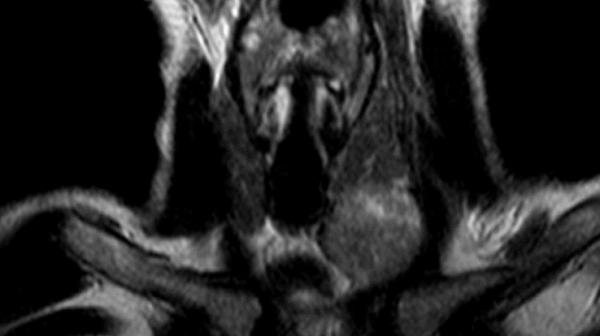

Рисунок 1,2. МРТ мягких тканей шеи (Т2-ВИ и Т1-fs-ВИ контрастное усиление). Патологических образований в структуры щитовидной железы не выявлено.

Снимки МРТ мягких тканей шеи

Мягкие ткани шеи на МРТ